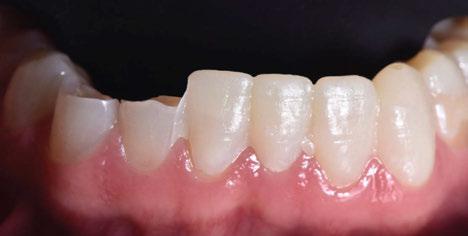

Figura 1. Caso inicial. Figura 2. Vista oclusal superior.

Figura 33. Vista oclusal superior. Figura 34. Vista oclusal maxilar Inferior. Figura 31. Restauraciones cementadas, vista anterior superior. Figura 32. Restauraciones cementadas, vista anterior inferior. Figura 35. Vista en oclusión del caso terminado.

CIENCIA Y CLÍNICA. Caso clínico